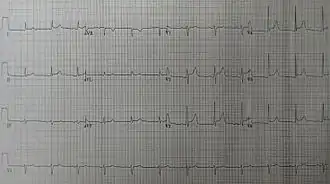

The preferred initial diagnostic testing is the ECG, which may demonstrate a 12-lead electrocardiogram with diffuse, non-specific, concave ("saddle-shaped"), ST-segment elevations in all leads except aVR and V1[11] and PR-segment depression possible in any lead except aVR;[11] sinus tachycardia, and low-voltage QRS complexes can also be seen if there is subsymptomatic levels of pericardial effusion. The PR depression is often seen early in the process as the thin atria are affected more easily than the ventricles by the inflammatory process of the pericardium.